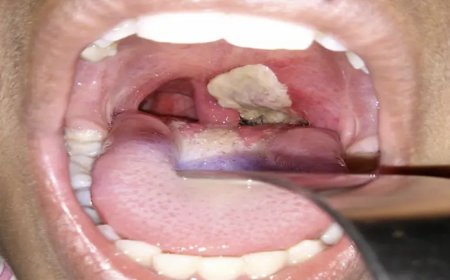

Tension Breaks Out In Abia After Diphtheria Hits Nearby...

There is palpable tension in Abia State, following the reported outbreak of Diph...